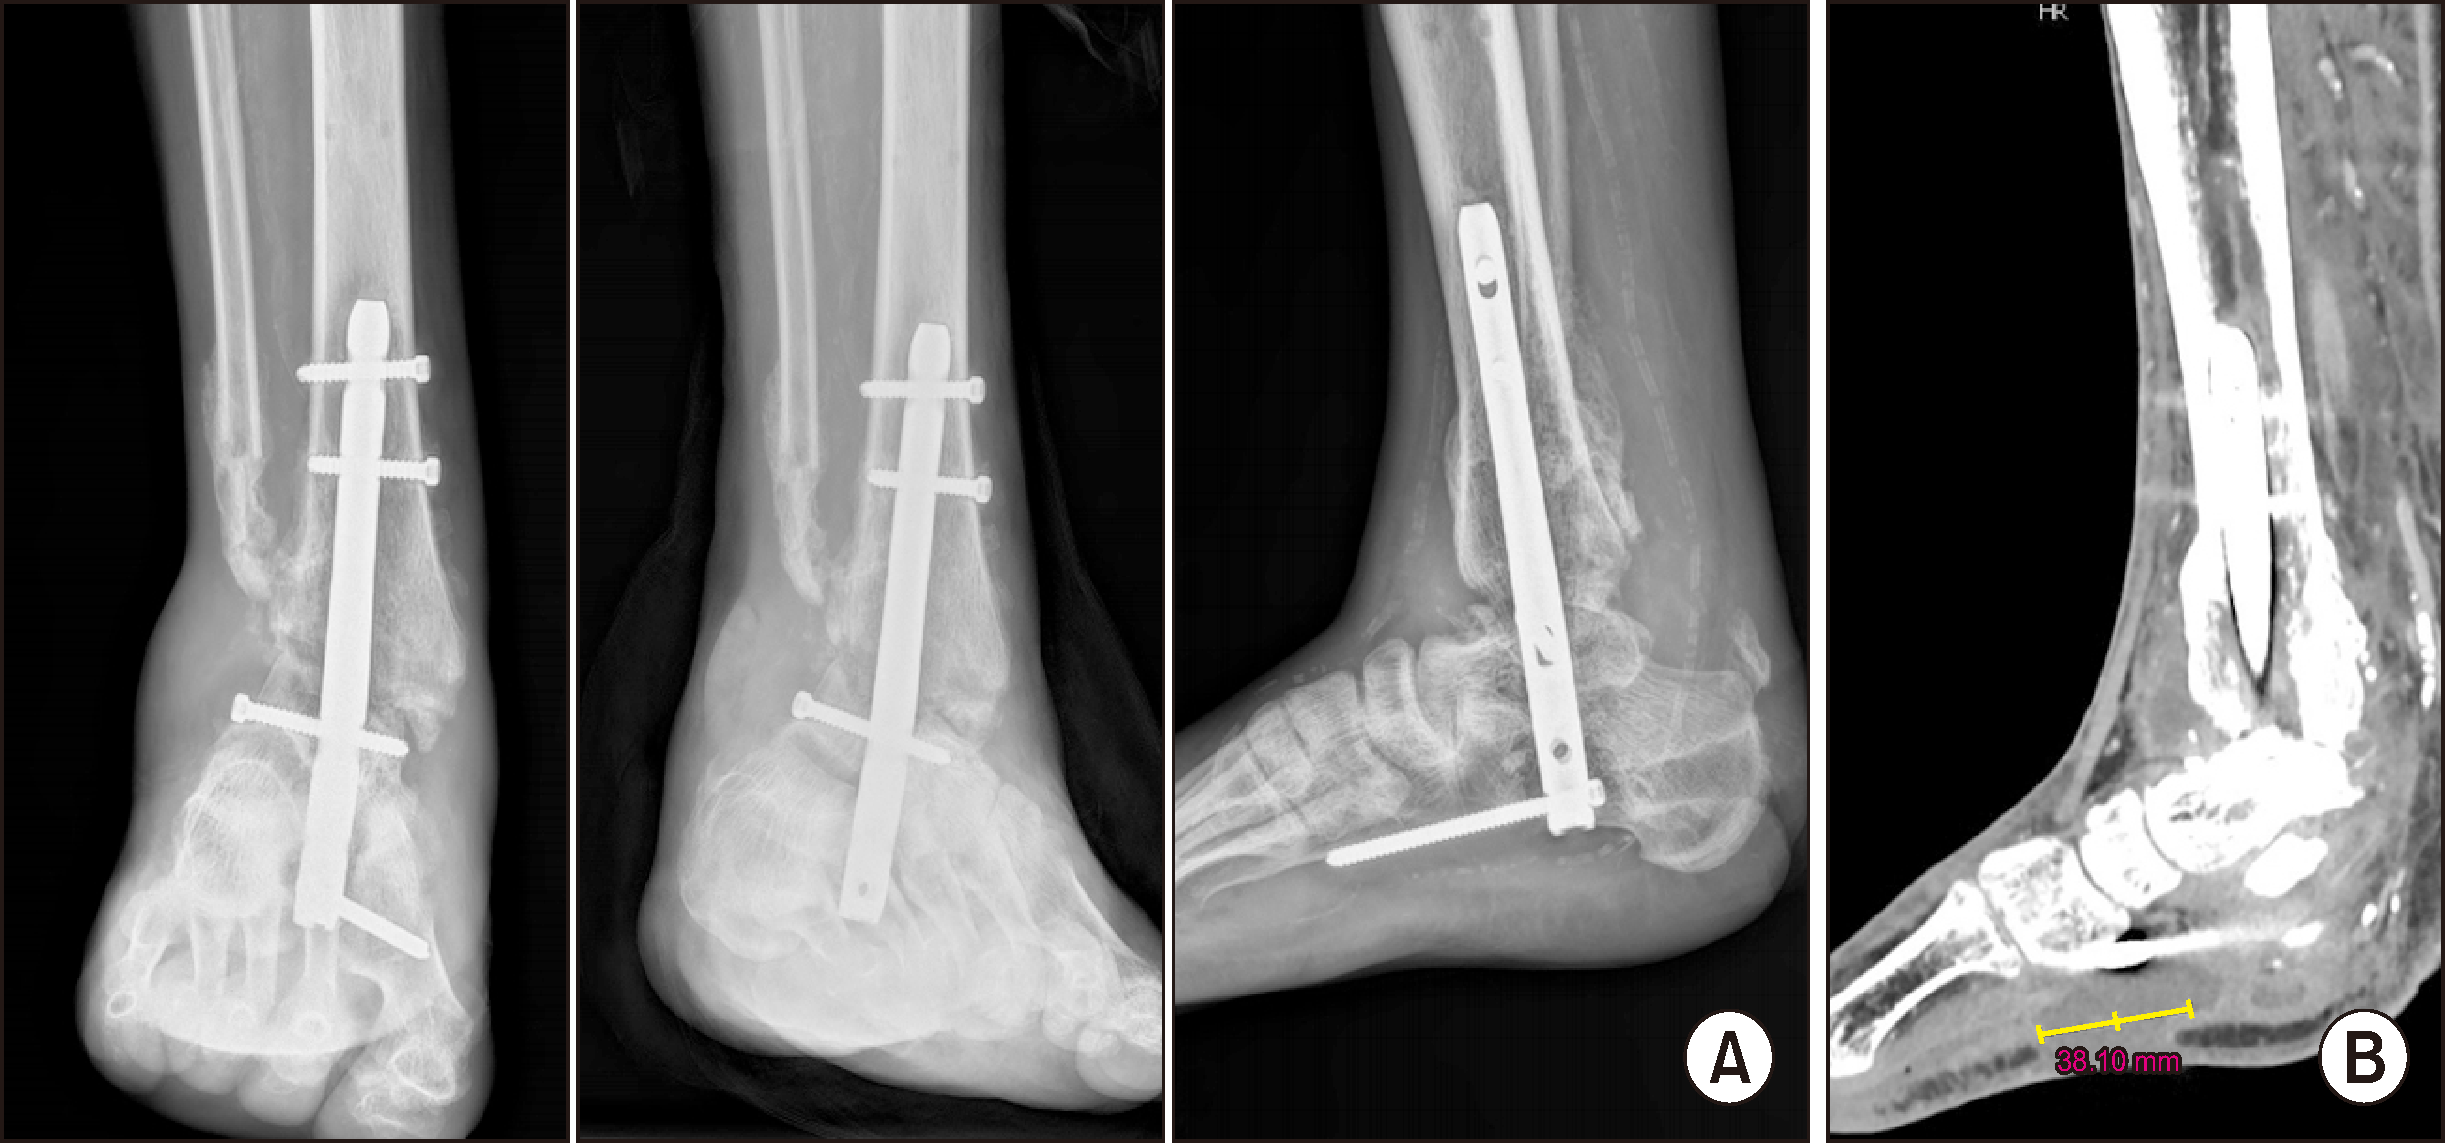

One week after applying the external fixator, tibiotalocalcaneal (TTC) fusion was performed using a retrograde T2 nail (T2 Alpha Retrograde Femur Nailing System, Stryker Corporation), and a fibular bone ostectomy was conducted to provide a bone graft at the fusion site (Fig. 7A). Additionally, there was a medial wound defect at the time of surgery, indicating the need for further interventions such as a flap in the future (Fig. 7B). Approximately 3 weeks after the TTC fusion, granulation tissue was observed in the medial wound. Kerecis GraftGuide (Kerecis Ltd.) was applied to cover the wound defect (Fig. 8).

Figure 7

(A) Post-operative radiograph after tibiotalocalcaneal fusion using a retrograde T2 nail. (B) Clinical findings showing a medial wound defect at the time of surgery.

(A) Radiograph at 3 months post-TTC fusion. (B) CT scan at 6 months post-TTC fusion showing soft tissue defect at the sole, extending posteriorly to form a sinus tract or abscess. TTC: tibiotalocalcaneal.